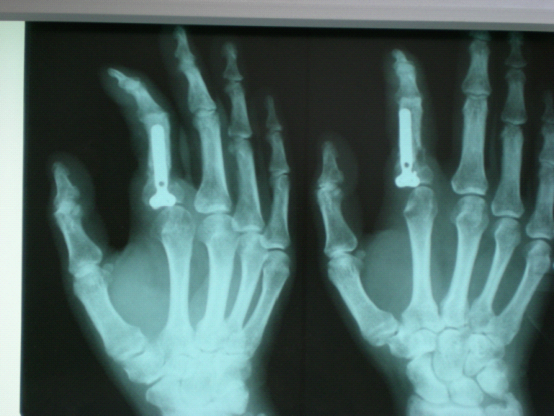

王某某,男,54岁,左示指近节指骨骨折在外院行切开复位钢板骨折内固定术,术后刀口感染,在外治疗一年余,无好转,来我院诊断为慢性骨髓炎,患者强烈要求截指。

治疗后